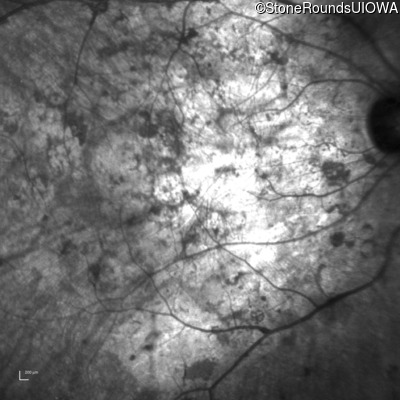

Infrared Fundus Photograph - Right - Hand Motion sc

Exemplar